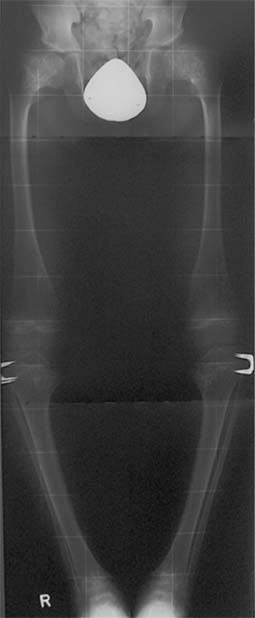

Gemeinsame Kennzeichen sind generalisierte Platyspondylie und Veränderungen der Metaphysen hauptsächlich an Hüft- und Kniegelenk.

- SMD Typ Schmidt oder algerischer Typ, autosomal-dominant vererbt, mit schwerem Genu valgum